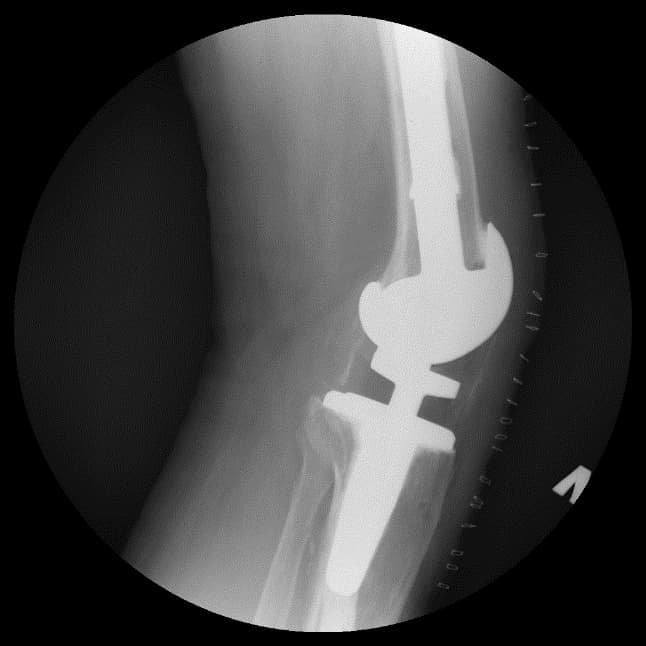

Үе дайрсан ясны анхдагч хавдар, ясны дутмагшлын үед хийгдэх мэс засалimg15Үе дайрсан ясны анхдагч хавдар, ясны дутмагшлын үед хийгдэх мэс засалimg16

Зураг 3. Мэс заслын дараах рентген зураг. Эгц урд, хажуугаас авсан байдал